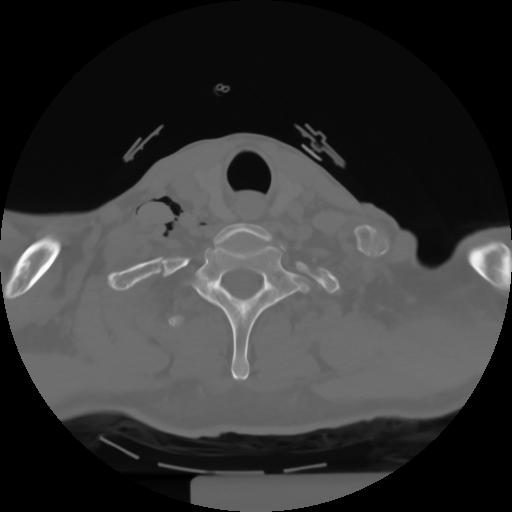

10 P.BLANDAS,,Axial,2.0,P.BLANDAS,,